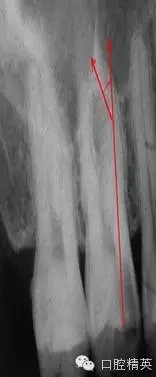

在根管治療的幾年經(jīng)驗(yàn)中,有些感悟愿與朋友們分享,不到的地方請(qǐng)同仁指正。在做好根管治療時(shí)我們首先要攝片分析根管難度選擇合適器具合適方法進(jìn)行治療,根管難度評(píng)估:簡(jiǎn)單根管(5-10度)

,中等難度根管,(10-25度)復(fù)雜難度根管(大于25度)